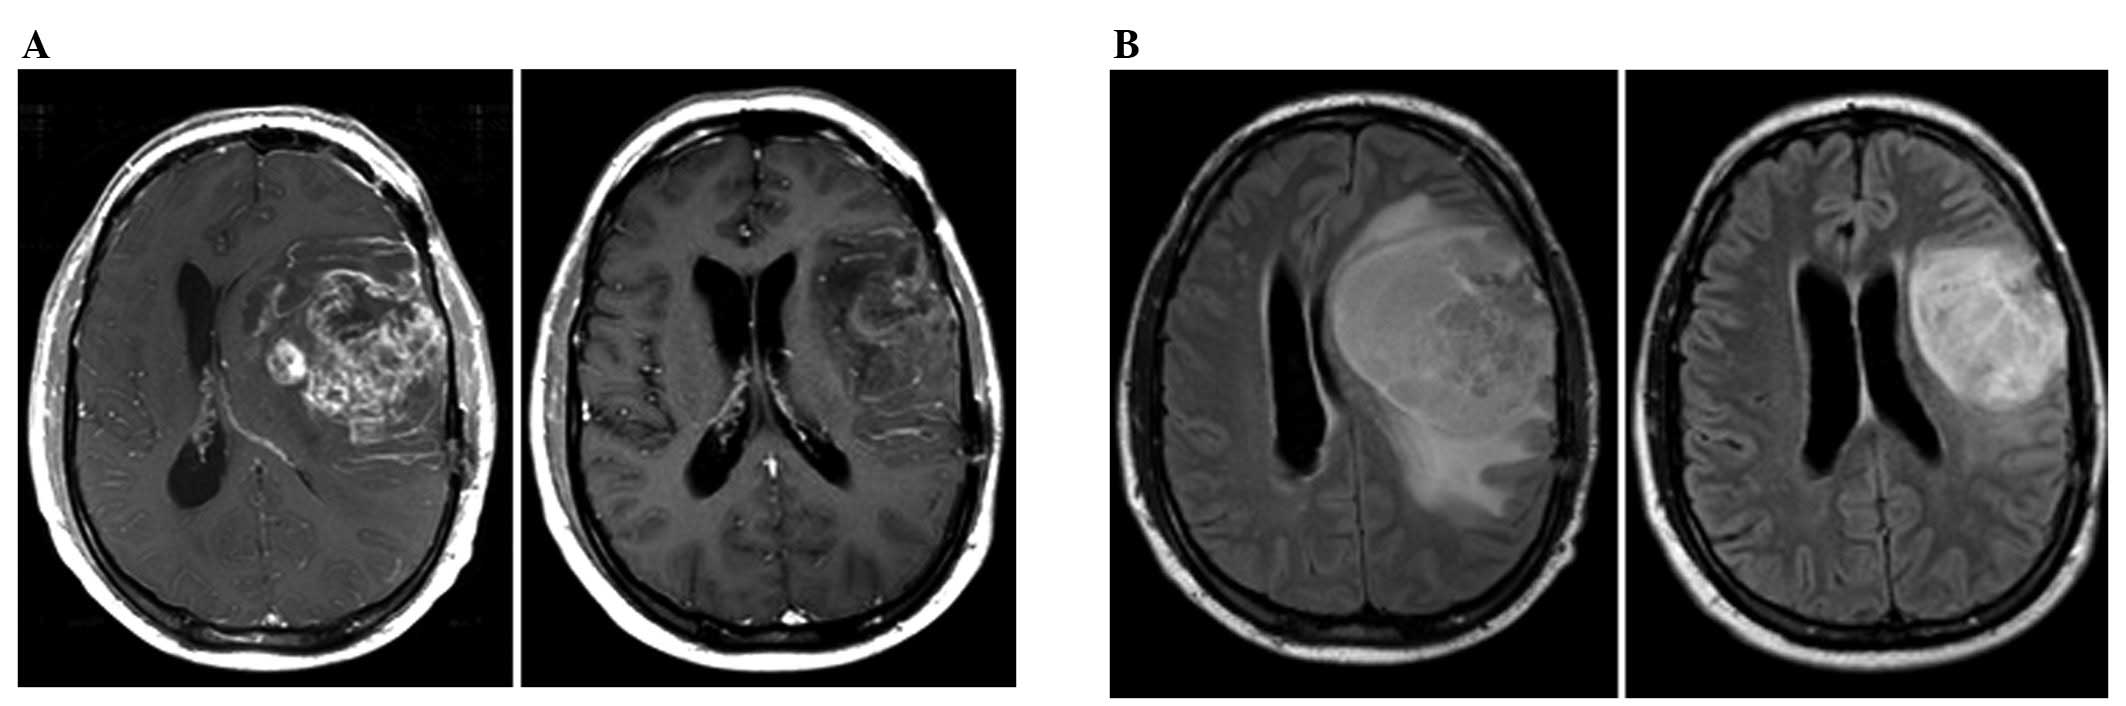

DISTINCTION BETWEEN RECURRENT GLIOMA AND RADIATION ... - U-System

DISTINCTION BETWEEN RECURRENT GLIOMA AND RADIATION INJURY USING MAGNETIC RESONANCE SPECTROSCOPY IN COMBINATION WITH DIFFUSION-WEIGHTED IMAGING QING-SHI ZENG,PH.D.,* CHUAN-FU LI, MR spectroscopy for recurrent glioma vs. radiation injury ... Access Doc

Glioma recurrence Versus Radiation Necrosis: Accuracy Of ...

Glioma recurrence versus radiation necrosis: accuracy of current imaging modalities between post-irradiation necrosis and recurrent glioma on the basis of clinical signs and symptomatology has not been possible. Computed tomography (CT) and magnetic ... Doc Viewer